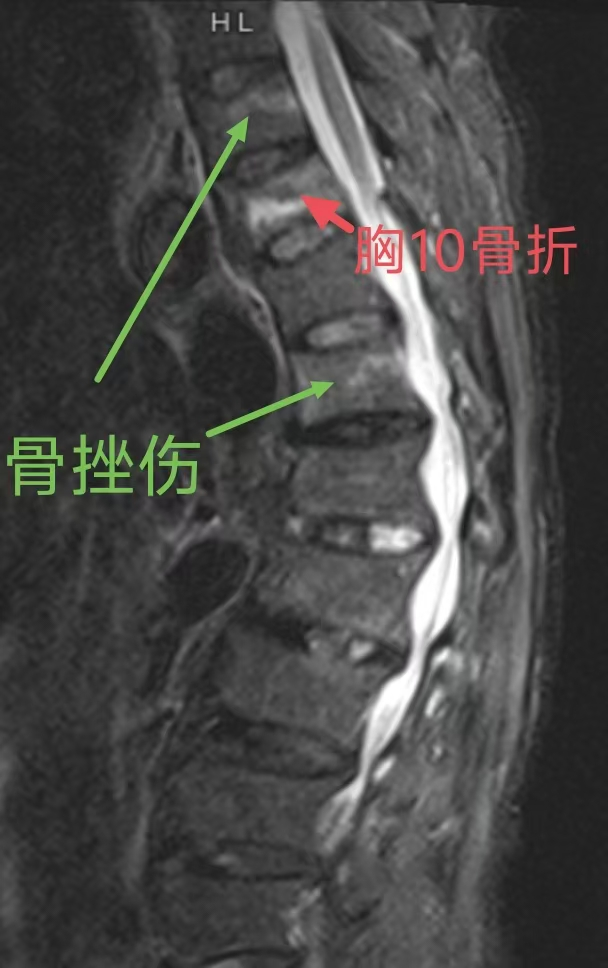

发现隐匿性病变,不做“冤大头”。临床上常有患者因剧烈腰痛前来就诊,但X光片显示骨头完好无损。过去,这可能会被简单地归结为“腰肌劳损”。而现在,磁共振能轻易发现X光和CT无法显示的早期骨髓水肿、隐匿性骨折以及早期椎间盘感染。这不仅能帮助患者找到真正的病因,避免了误诊误治,也大大提升了医院处理复杂脊柱创伤和感染性疾病的能力。

(CT发现胸10骨折,磁共振发现胸9、12损伤)

为手术装上“导航”,提升安全系数。在脊柱肿瘤或脊髓损伤的治疗中,磁共振的价值更为凸显。它不仅能显示肿瘤的边界及其与周围重要神经、血管的关系,还能评估脊髓本身的水肿、出血或断裂情况。这使得医生在切除病灶时,能够像拥有导航仪一样,在最大程度保护神经功能的前提下,精准切除病灶,大大降低了瘫痪等严重并发症的风险。